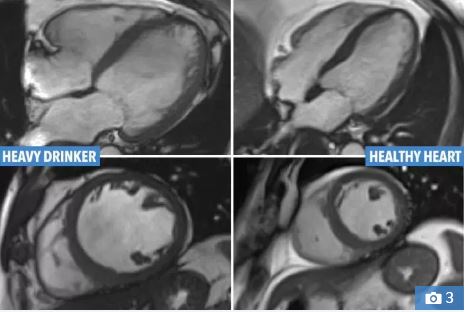

The left picture shows the enlarged heart of someone with alcoholic cardiomyopathy, compared to a healthy heart on the right hand side

Shocking pictures show the difference between a healthy heart and the heart of someone who drinks too much.

It shows the enlarged heart of someone suffering from alcoholic cardiomyopathy (ACM), which causes the heart to swell and lose the ability to properly pump blood around the body.